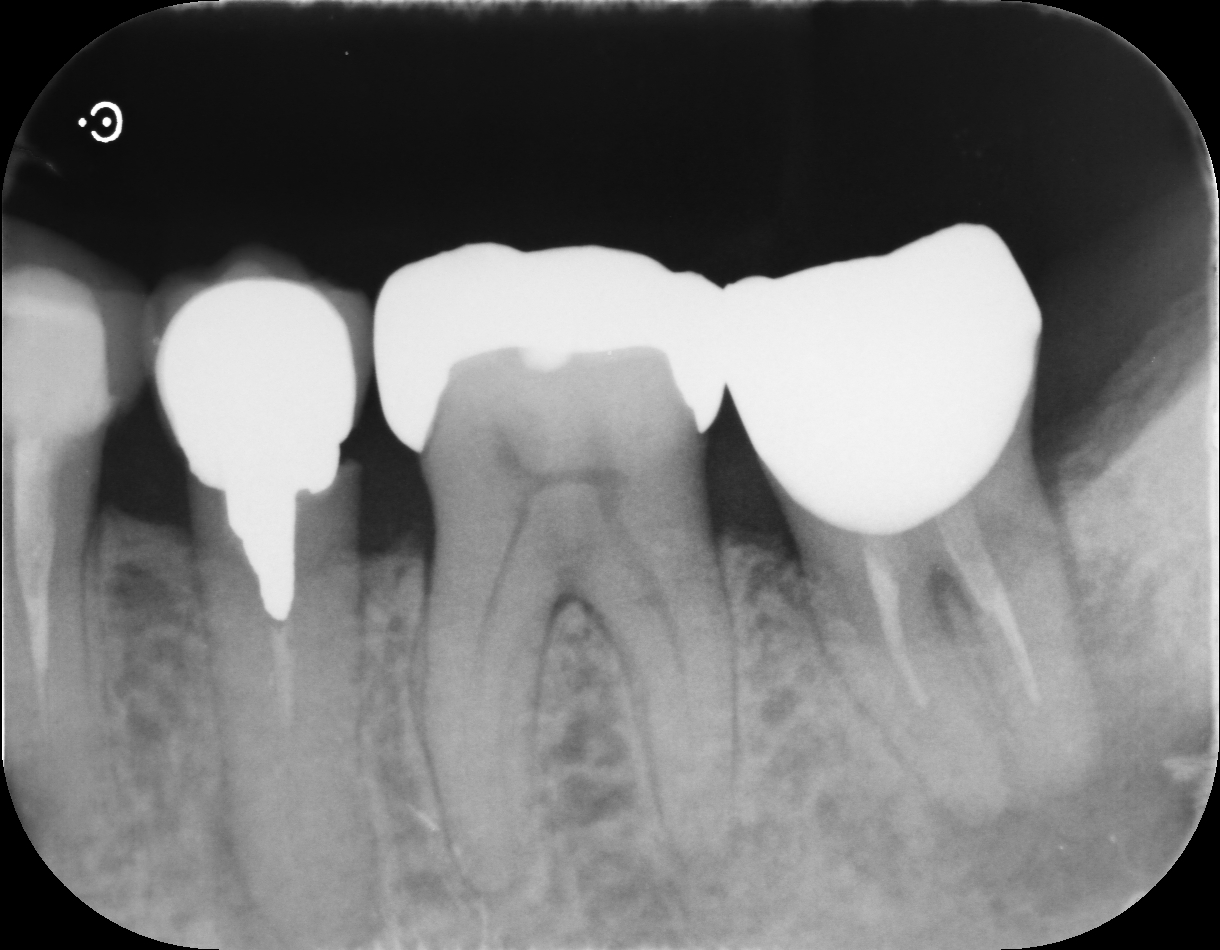

• after

根管内が清潔になったことを確認した後、薬剤を充填し、最終的に被せ物などで歯を補強します。

根管治療、補綴治療

オールセラミッククラウン ¥198,000-

感染根幹治療 (大臼歯)¥132,000-,(小臼歯)¥110,000-